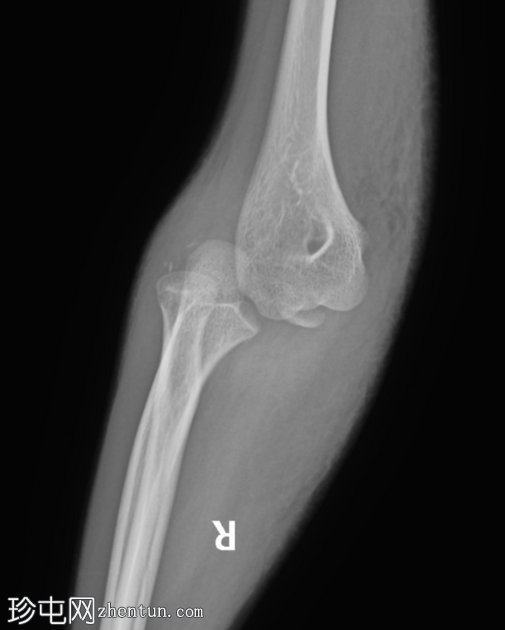

术后

X线片

5.png

正位片

侧位片

使用空心螺钉对内上髁进行有效复位。

位置良好的硬物